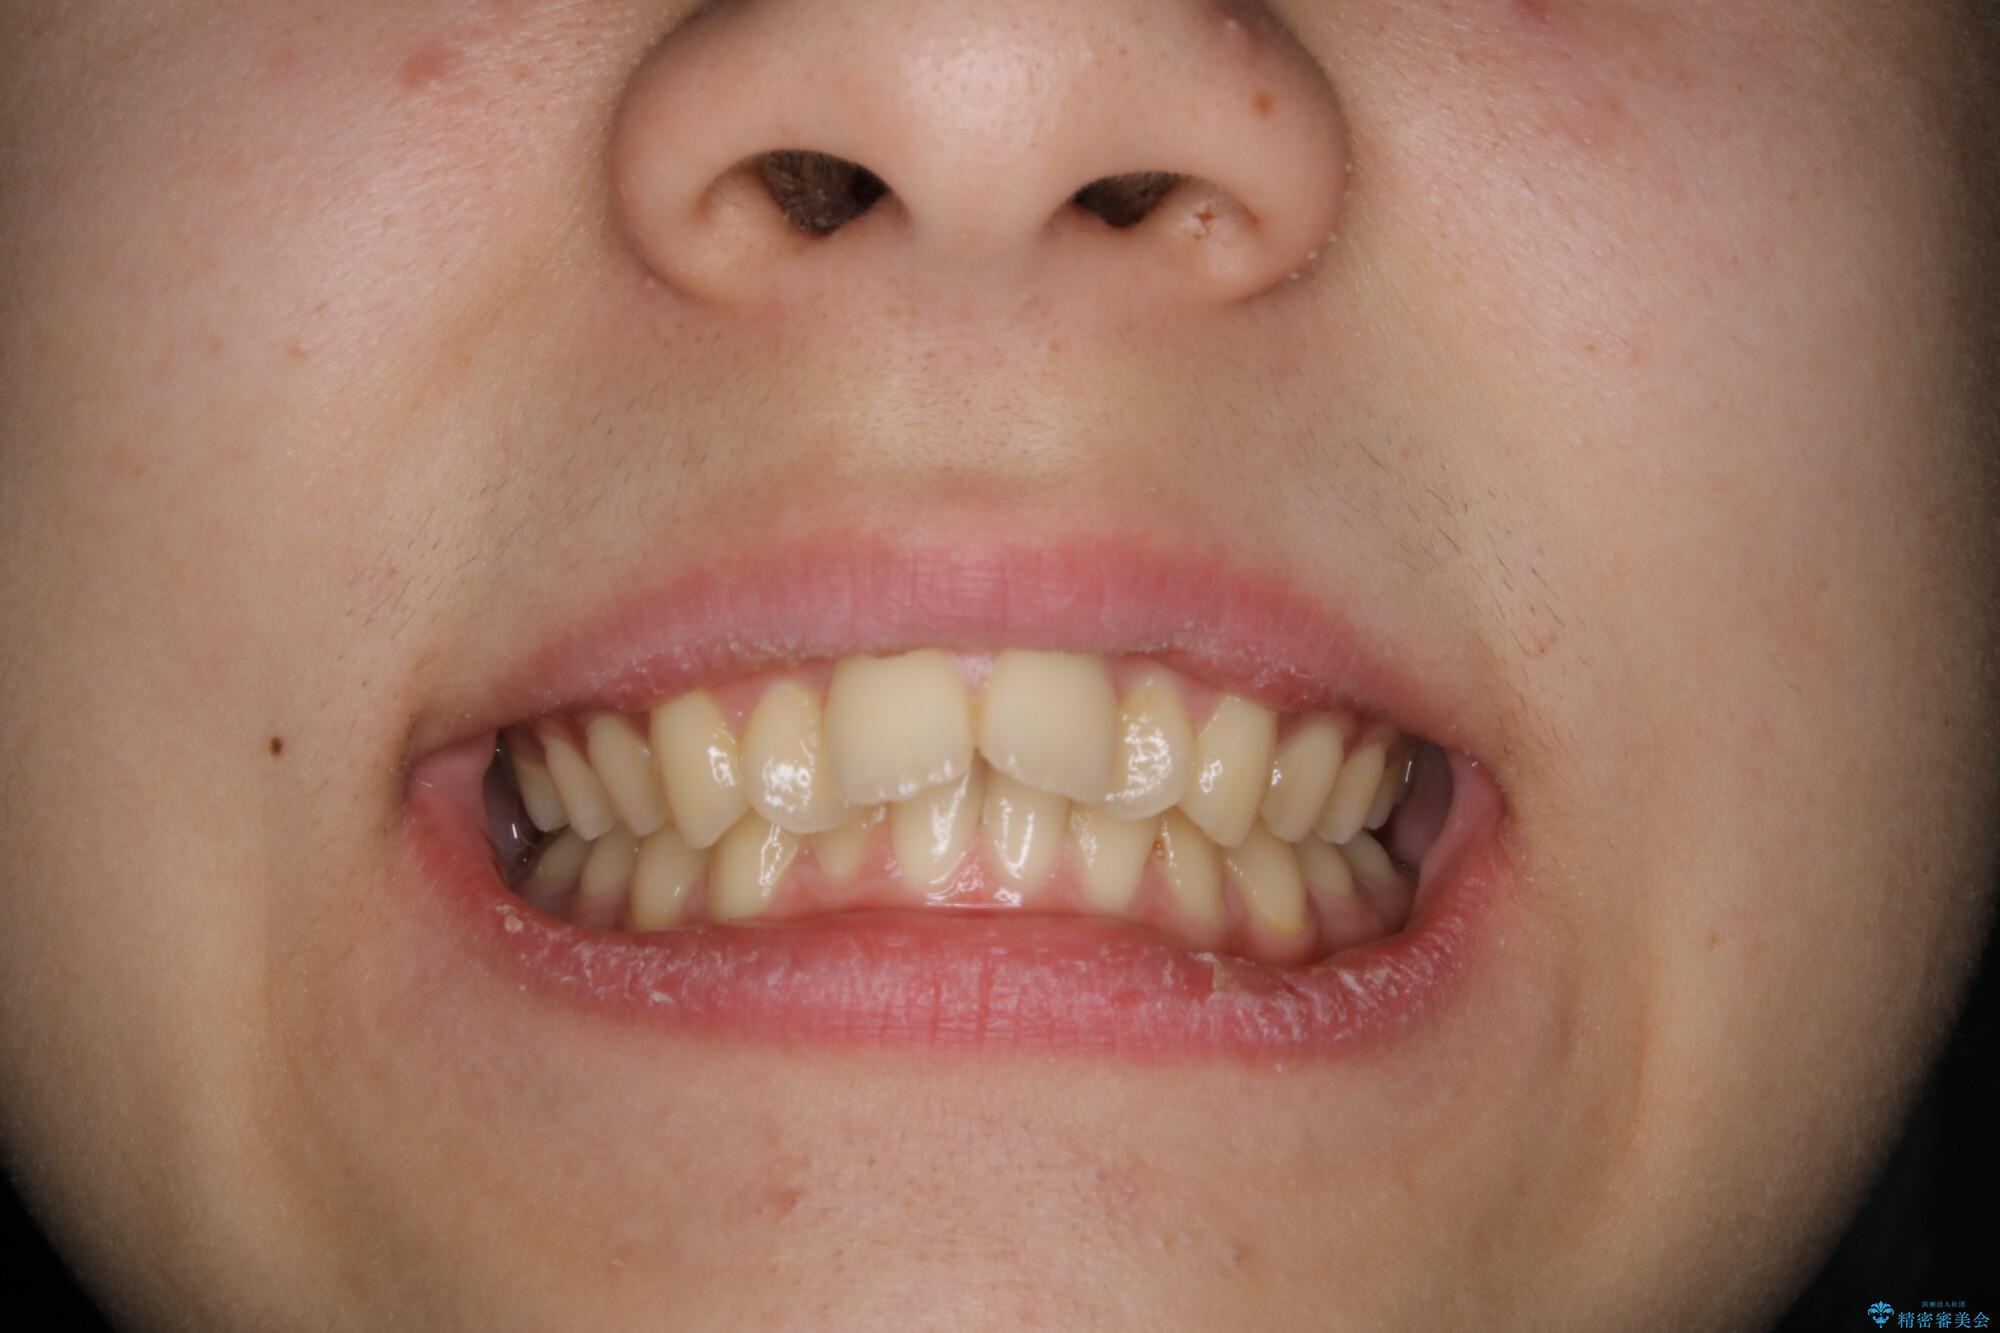

- 患者様、出っ歯のお悩みで来院されました。

骨格の分析を行ったところ上顎も出てはいるのですが、下顎が引っ込んでいる状態であるということがわかりました。

よって上顎の歯を抜いて治療をするのではなく、カリエールという器具を使用して下顎を前に引っ張り出しながら上顎を引っ込めるという治療を行うことにしました。

ひと口に出っ歯(上顎前突)といっても原因は多様です。

骨格的な問題があるのか、歯だけの問題なのか、上顎が出ているのか、下顎が出ているのか。あるいはその両方か。

きちんと原因を見極めたうえで治療を開始しないと仕上がりは理想的になりません。

矯正検査を行い、しっかりと矯正診断を行った上で治療を開始することが大事です。